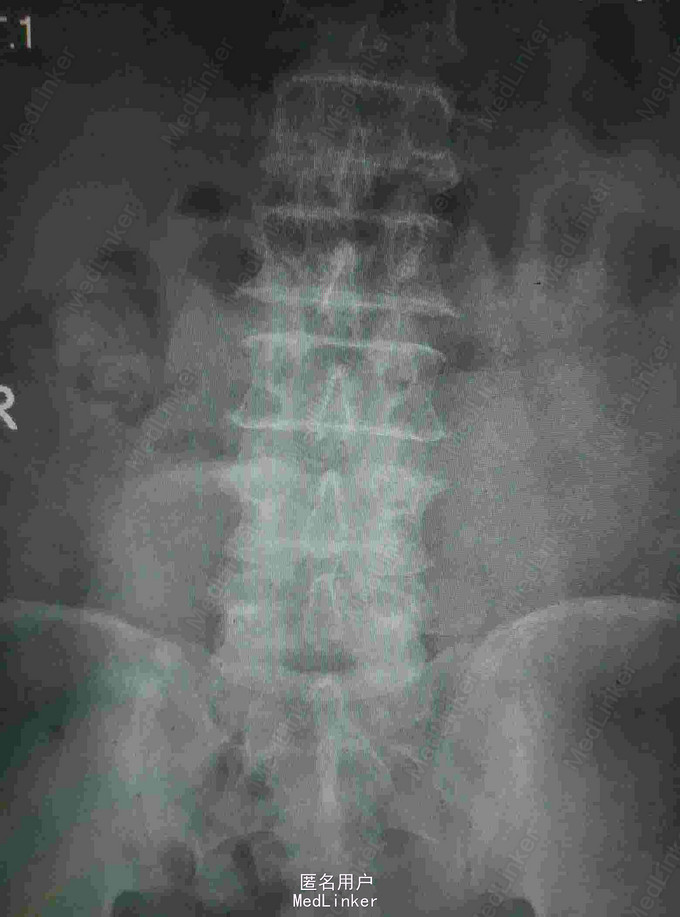

腰痛4年,双下肢麻痛无力伴二便障碍1月 患者老年男性,四年前无明显诱因出现腰痛,当时无双下肢麻痛及大小便障碍。四年来症状反复发作,未做特殊处理,近一月来患者腰痛症状加重,出现双下肢麻痛无力,伴有大小便障碍,为进一步治疗入我院。

查体:患者腰围固定,腰骶部及椎旁可有轻压痛,双侧臀部及大腿外侧放射痛,双下肢肌力减退,膝踝反射减弱 辅查:我院CT及外院核磁提示L4-5椎间盘向后膨出伴椎管重度狭窄,马尾神经受压

诊断:腰椎间盘突出 马尾神经受压 双下肢不全瘫 治疗:腰椎后路减压植骨融合内固定术